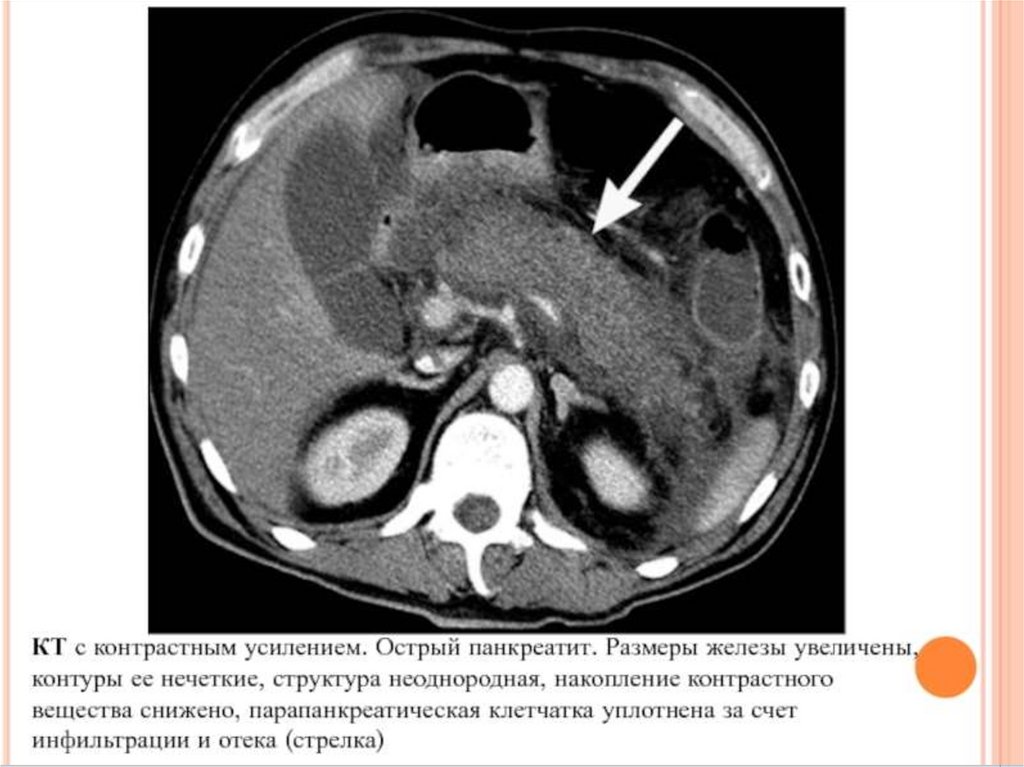

ОСТРЫЙ ПАНКРЕАТИТ